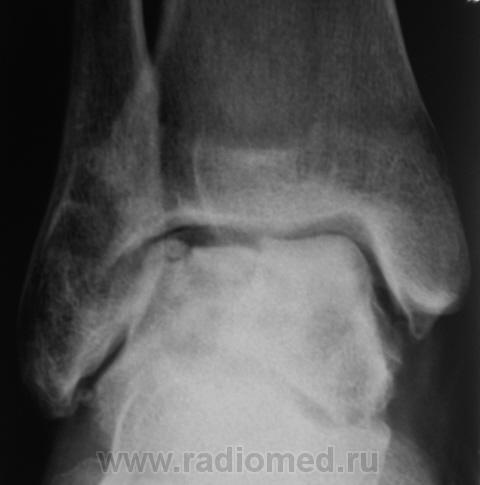

Пациент направлен на рентгенографию голеностопного сустава с диагнозом ДОА.

После внутрисуставного перелома вероятность доа оччень высока. Колгда была травма?

Травма была два года тому.

Похоже  на  остеохондропатию  блока  таранной  кости  +   ДОА.

А присутствует линейный (или лентовидный, я их путаю) остеопороз, а это признак острого процесса.

+ за лентовидный остеопроз...

Будем думать, что некроз блока таранной кости не такой уж и асептический, какая-то инхвекция там есть.

Посттравматический артроз с кистовидной перестройкойлатерального мыщелка Субхондральное уплотнение исужение суст. щелей естьИ неконгруэнтность большеберцового эпифиза к таранной маленько просматривается?